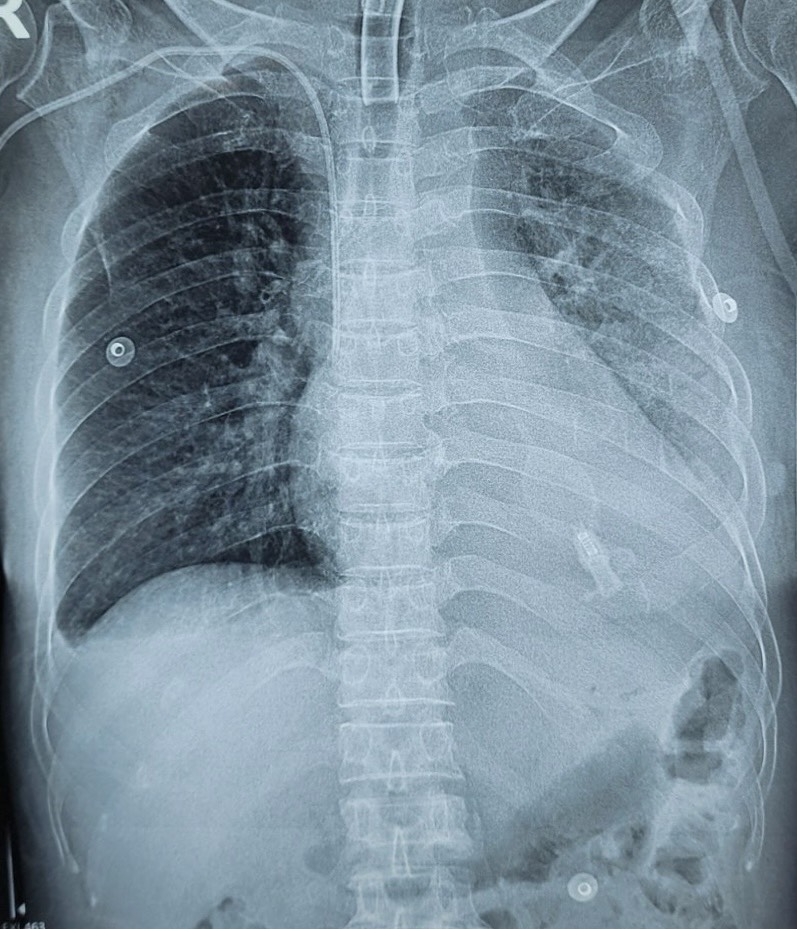

Trường hợp bệnh nhân nữ, 63 tuổi, tiền sử khoẻ mạnh. Sau tai nạn giao thông xe máy – xe máy, bệnh nhân chấn thương cột sống cổ, tổn thương tuỷ cổ đoạn cao, đã được phẫu thuật giải phóng chèn ép, còn liệt cơ hô hấp, liệt tứ chi, rối loạn cơ tròn, biến chứng viêm phổi, vào khoa trong tình trạng tỉnh, sốt cao 38-39 độ C, tăng tiết nhiều đờm vàng đặc qua mở khí quản, thông khí phổi kém, phụ thuộc hoàn toàn vào máy thở.

Cải thiện XQ trên bệnh nhân viêm phổi – chấn thương tuỷ cổ